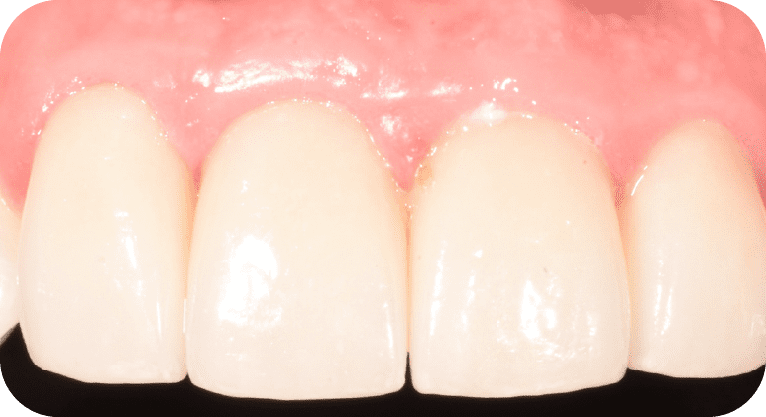

Paciente femenino, “29” años

Tratamiento: Carillas dentales

El paciente acudió a la clínica dental por inconformidad con la forma y posición de sus dientes. Tras una evaluación personalizada, se realizó un diseño de sonrisa con carillas dentales para mejorar su estética dental, logrando resultados naturales y satisfactorios.